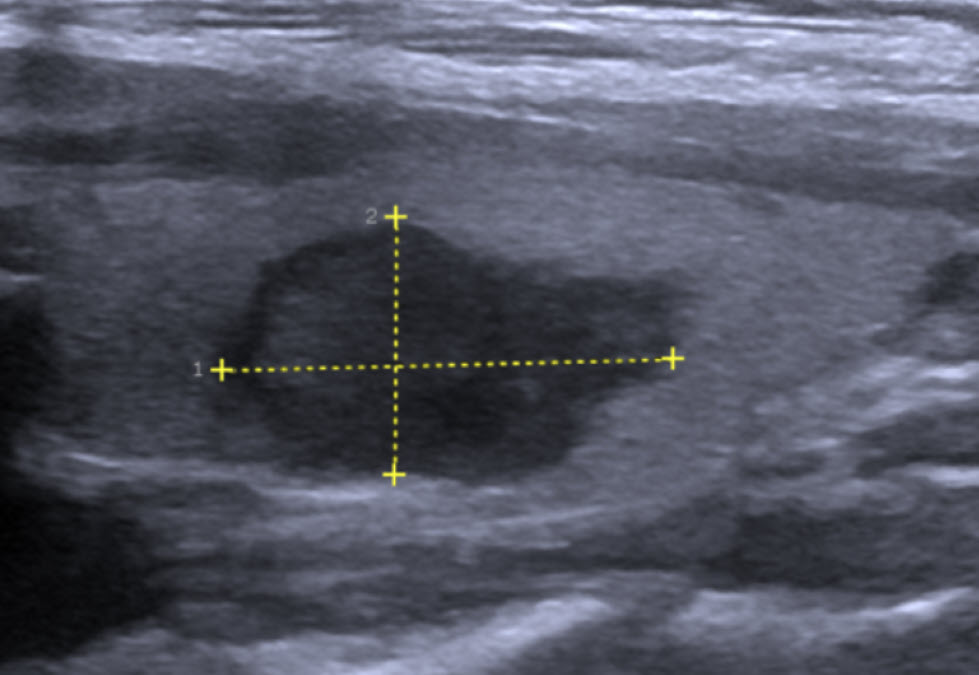

Khối u tuyến giáp thể nhú trên phim siêu âm: Hình ảnh giúp phát hiện và đánh giá kích thước, cấu trúc u, là bước đầu quan trọng trong chẩn đoán ung thư tuyến giáp.

- Siêu âm tuyến giáp: Là phương pháp đầu tay để đánh giá đặc điểm của khối u. Các dấu hiệu nghi ngờ ác tính bao gồm vi vôi hóa, rìa không đều, tăng sinh mạch máu trung tâm...